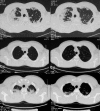

Figures